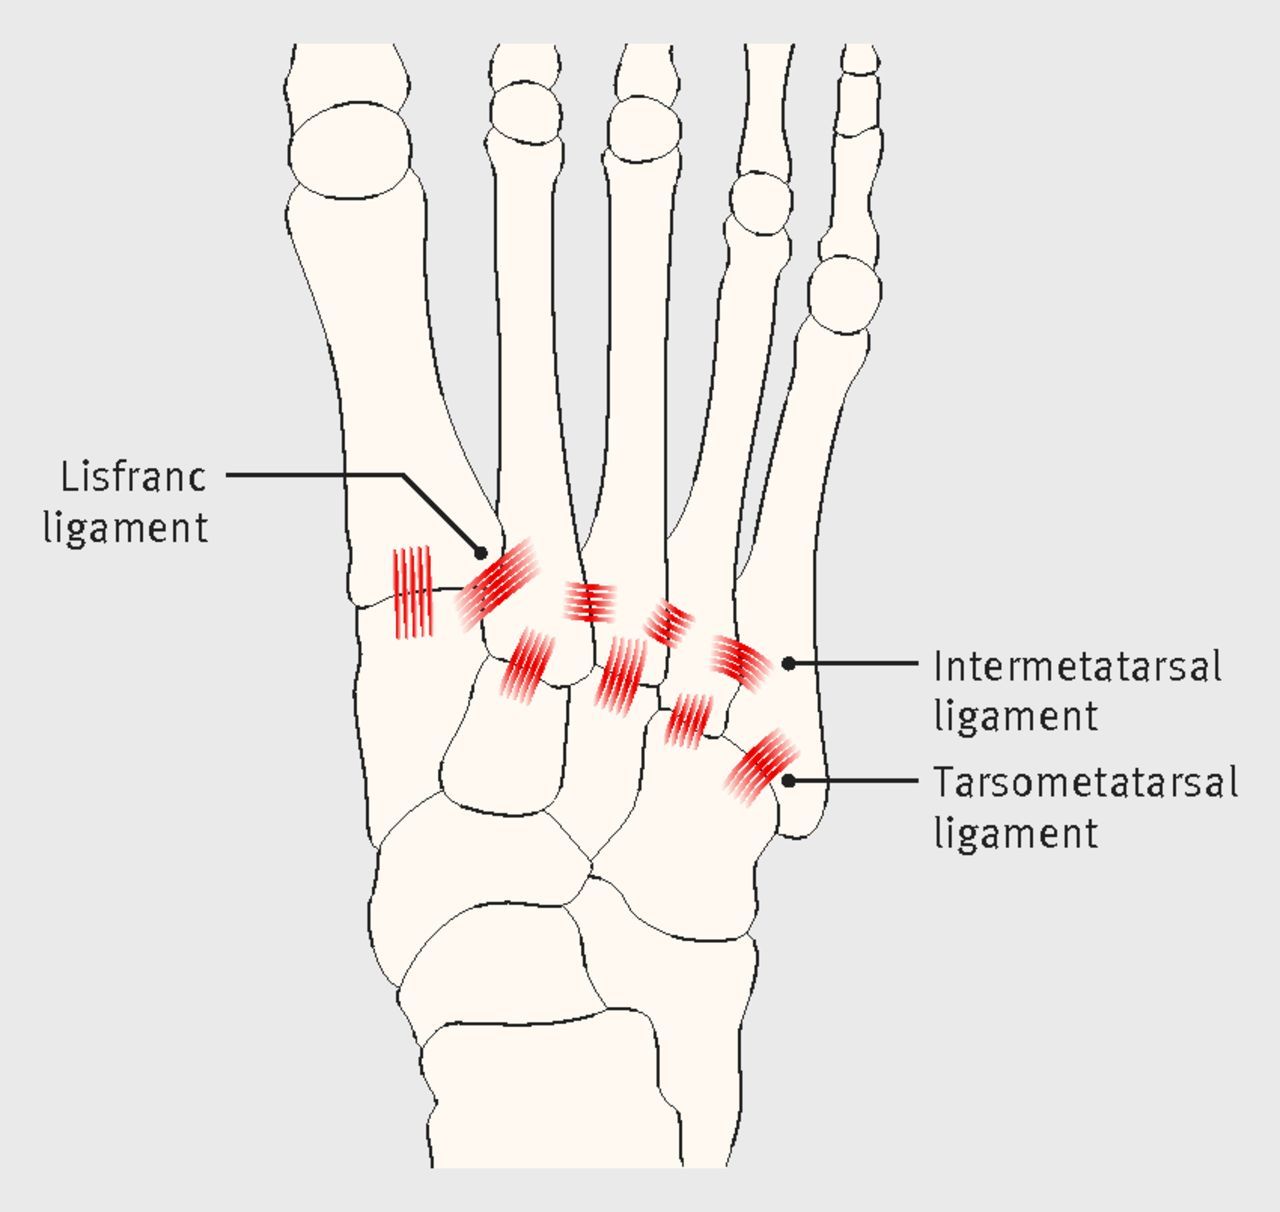

What is a Lisfranc injury?

Injury to tarsometatarsal joint between the medial cuneiform and the base of the 2nd metatarsal; can be solely ligamentous injuries or involve the bony structures of the midfoot (in which case called a fracture dislocation)

Why does a lisfranc injury occur between medial cuneiform & 2nd metatarsal